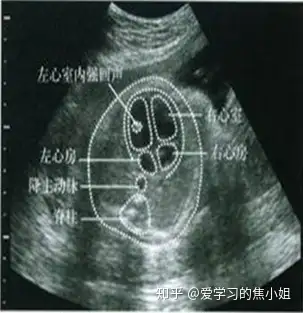

七、胎儿心血管系统异常

心内灶状强回声EIF:是心脏乳头肌内的微小钙化点。表现:胎儿心内大小不等,约2-7mm斑点状、条索状接近骨骼的强回声,不伴声影。

临床意义:正常胎儿中也较常见( 3%-5% ),不引起心脏的功能缺陷,不增加心脏结构异常的风险。右心室内多个EIF有显著意义,孤立性EIF与染色体异常及心脏畸形无相关性。